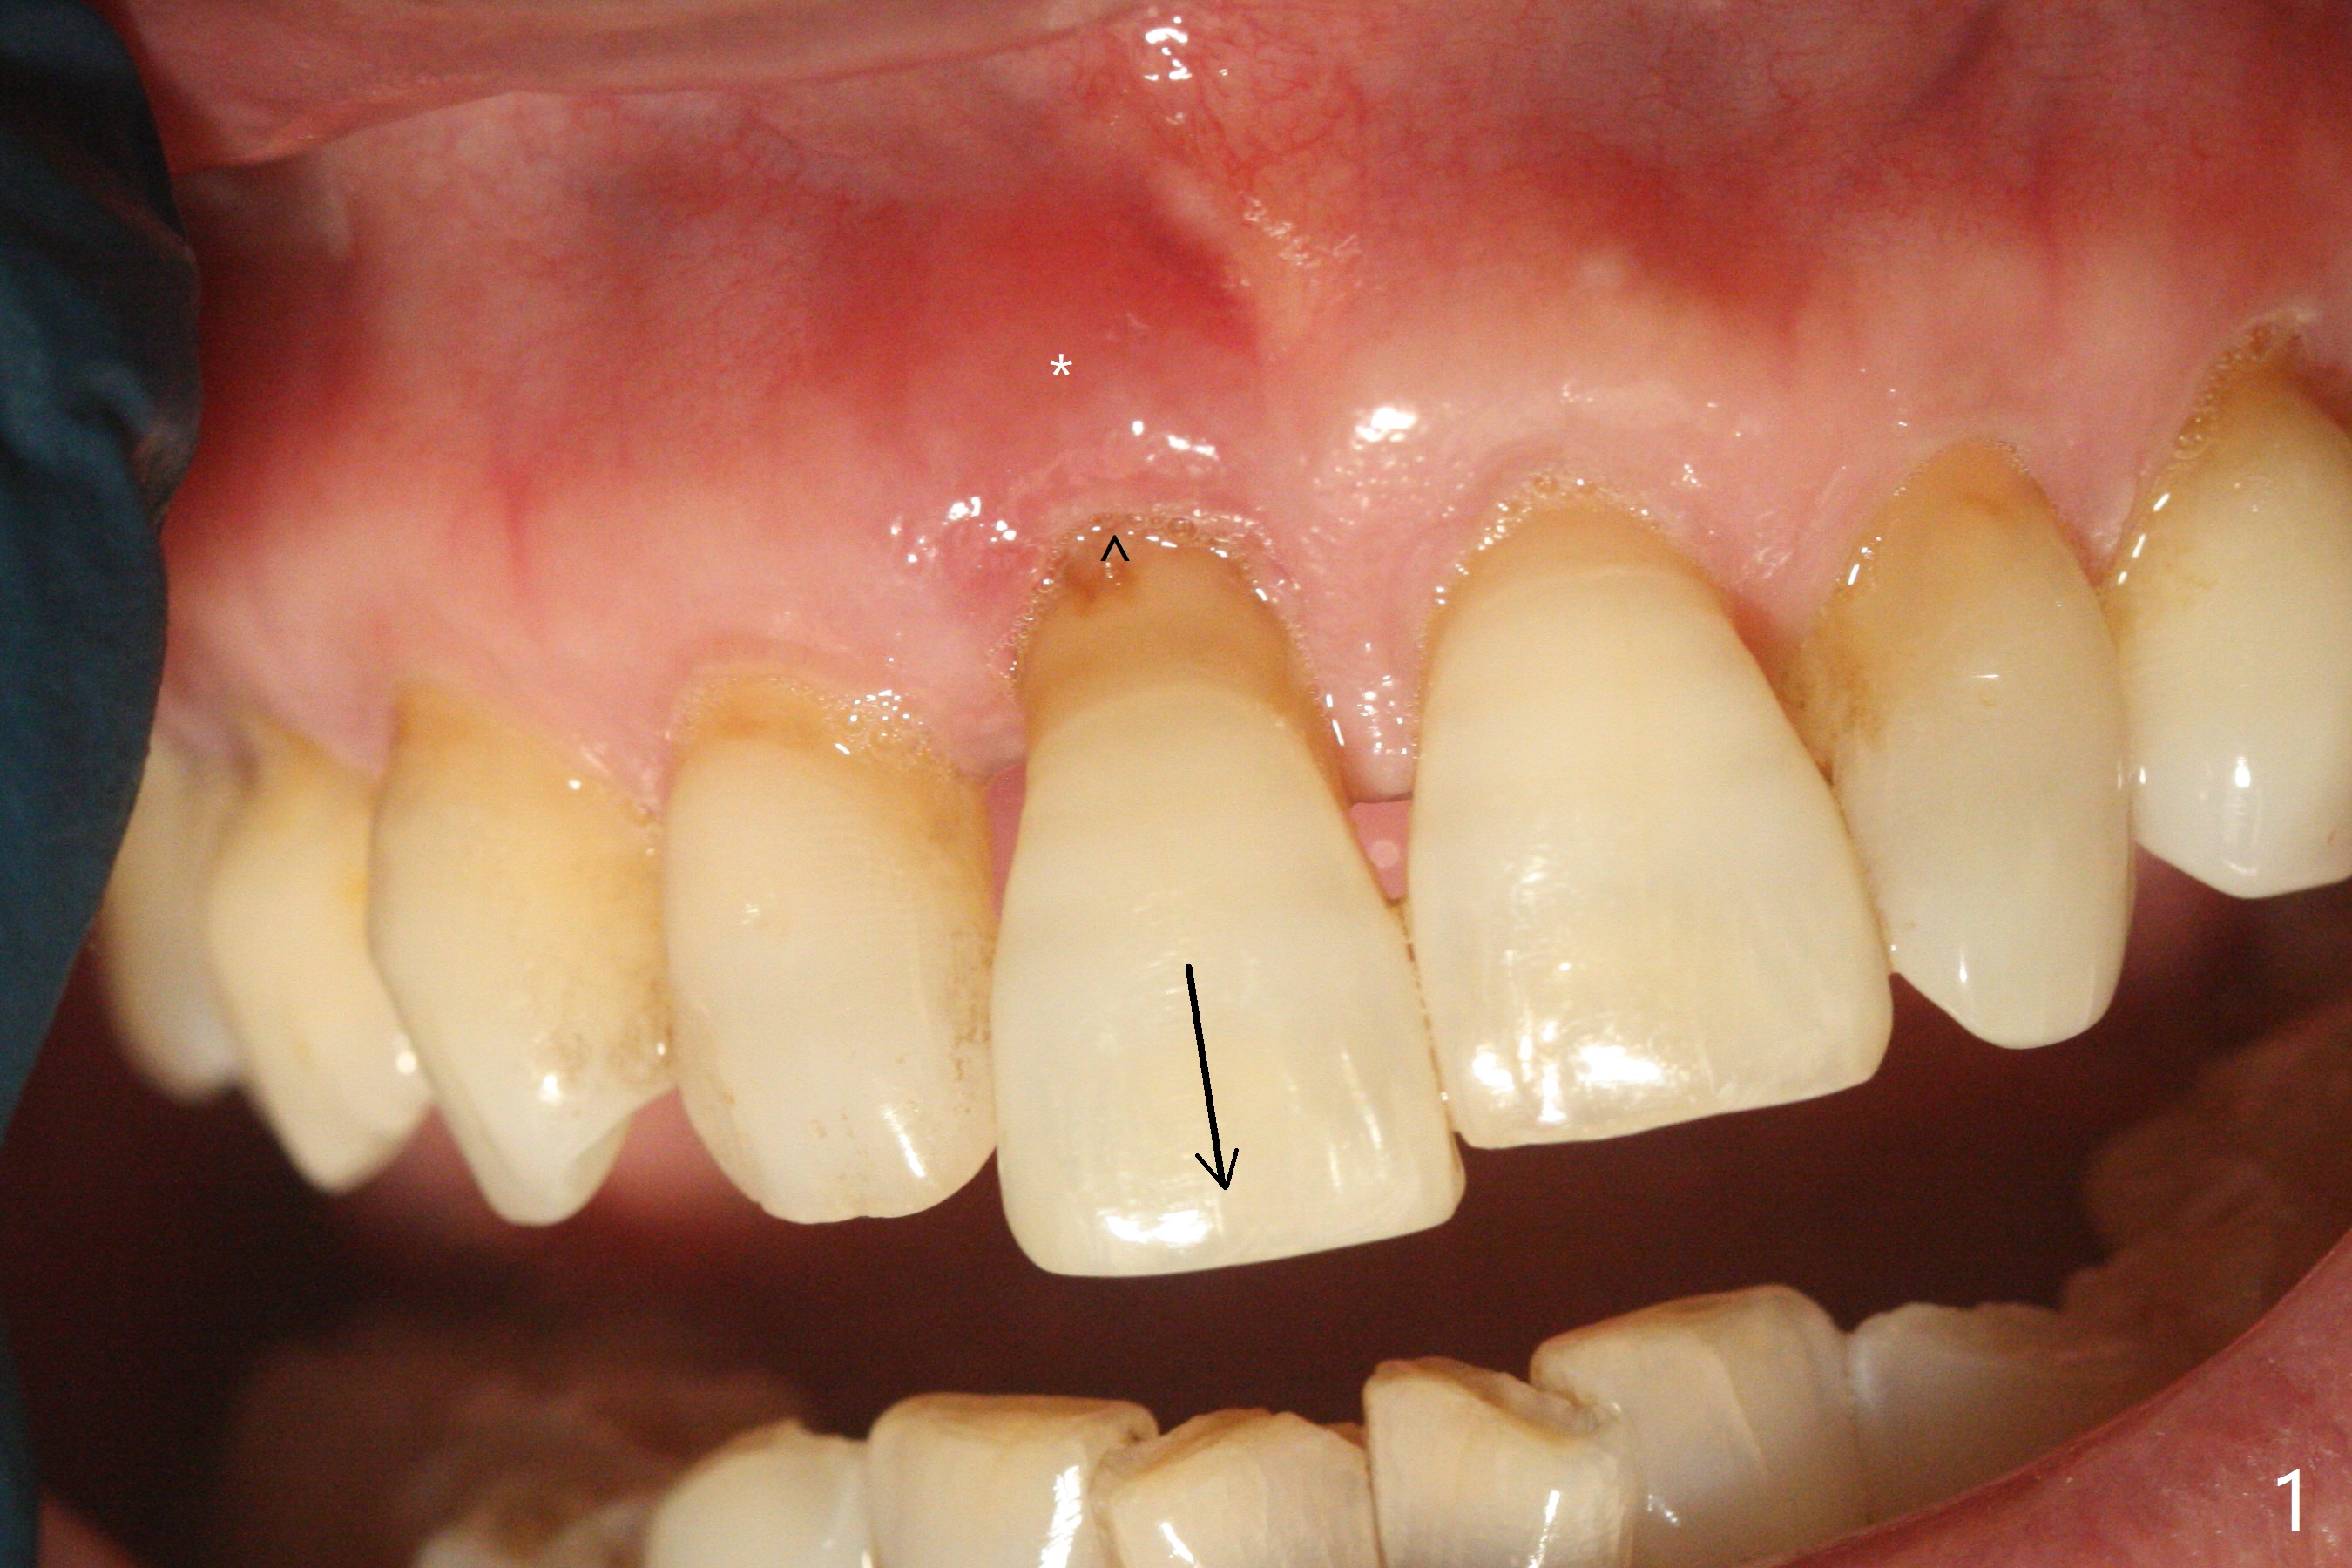

59岁女今天就诊,“上门牙快掉下来”,检查表明右上1延长(图一:长箭头),牙龈退缩(短箭头),红肿(*),颊侧骨板触诊不觉得塌陷(图二)。咬合时,患牙前移(图三),伸长的下切牙(图三,九:1,2)造成咬合创伤。因此拔牙前,将降低下门牙切缘(图四,五(黑色)),为临时牙冠创造足够修复空间。CT冠状切面显示颊侧(图六:B)骨板缺失,可以植入两段式植体(3.5x11.5 毫米),但是最细基台(4毫米直径,图七(粉红色和蓝色))显得太粗,不利于腭侧修复空间形成,而2.5x14(4)毫米一段式植体不仅创造更多颊侧植骨空间(图八(红箭头)),而且由于固有基台直径小(白箭头),容易形成腭侧修复空间。一旦前牙植体永久性修复完成,督促病人做三个第二磨牙植牙修复(图九:7),减少对前牙植牙创伤。临时牙冠不仅解决美观问题,而且固定骨粉,保持颊侧骨板隆起,维持牙龈缘和乳头。在大多数情况下,使用现成树脂牙冠(crown form)制作临时修复物,这个病例牙齿完整,截除的牙冠可以用来做临时牙冠。